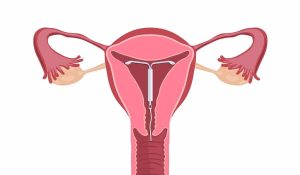

Intrauterine Device (IUD) or Intrauterine Contraceptive (IUC)

An intrauterine device or an intrauterine contraceptive is a small device inserted in a woman’s uterus to prevent pregnancy.